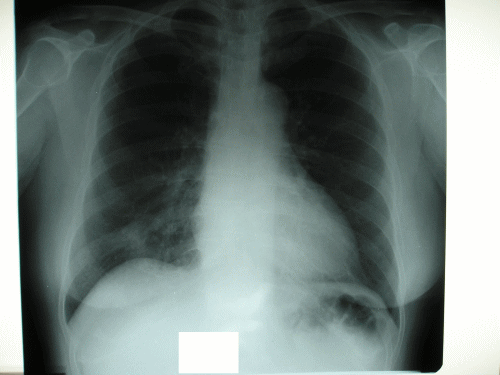

右 S10 の肺胞上皮癌。

無症状で 検診にて 発見。

無事に 下葉切除 終了し

術後診断にて Stage 1A

pT1N0M0 とされる。